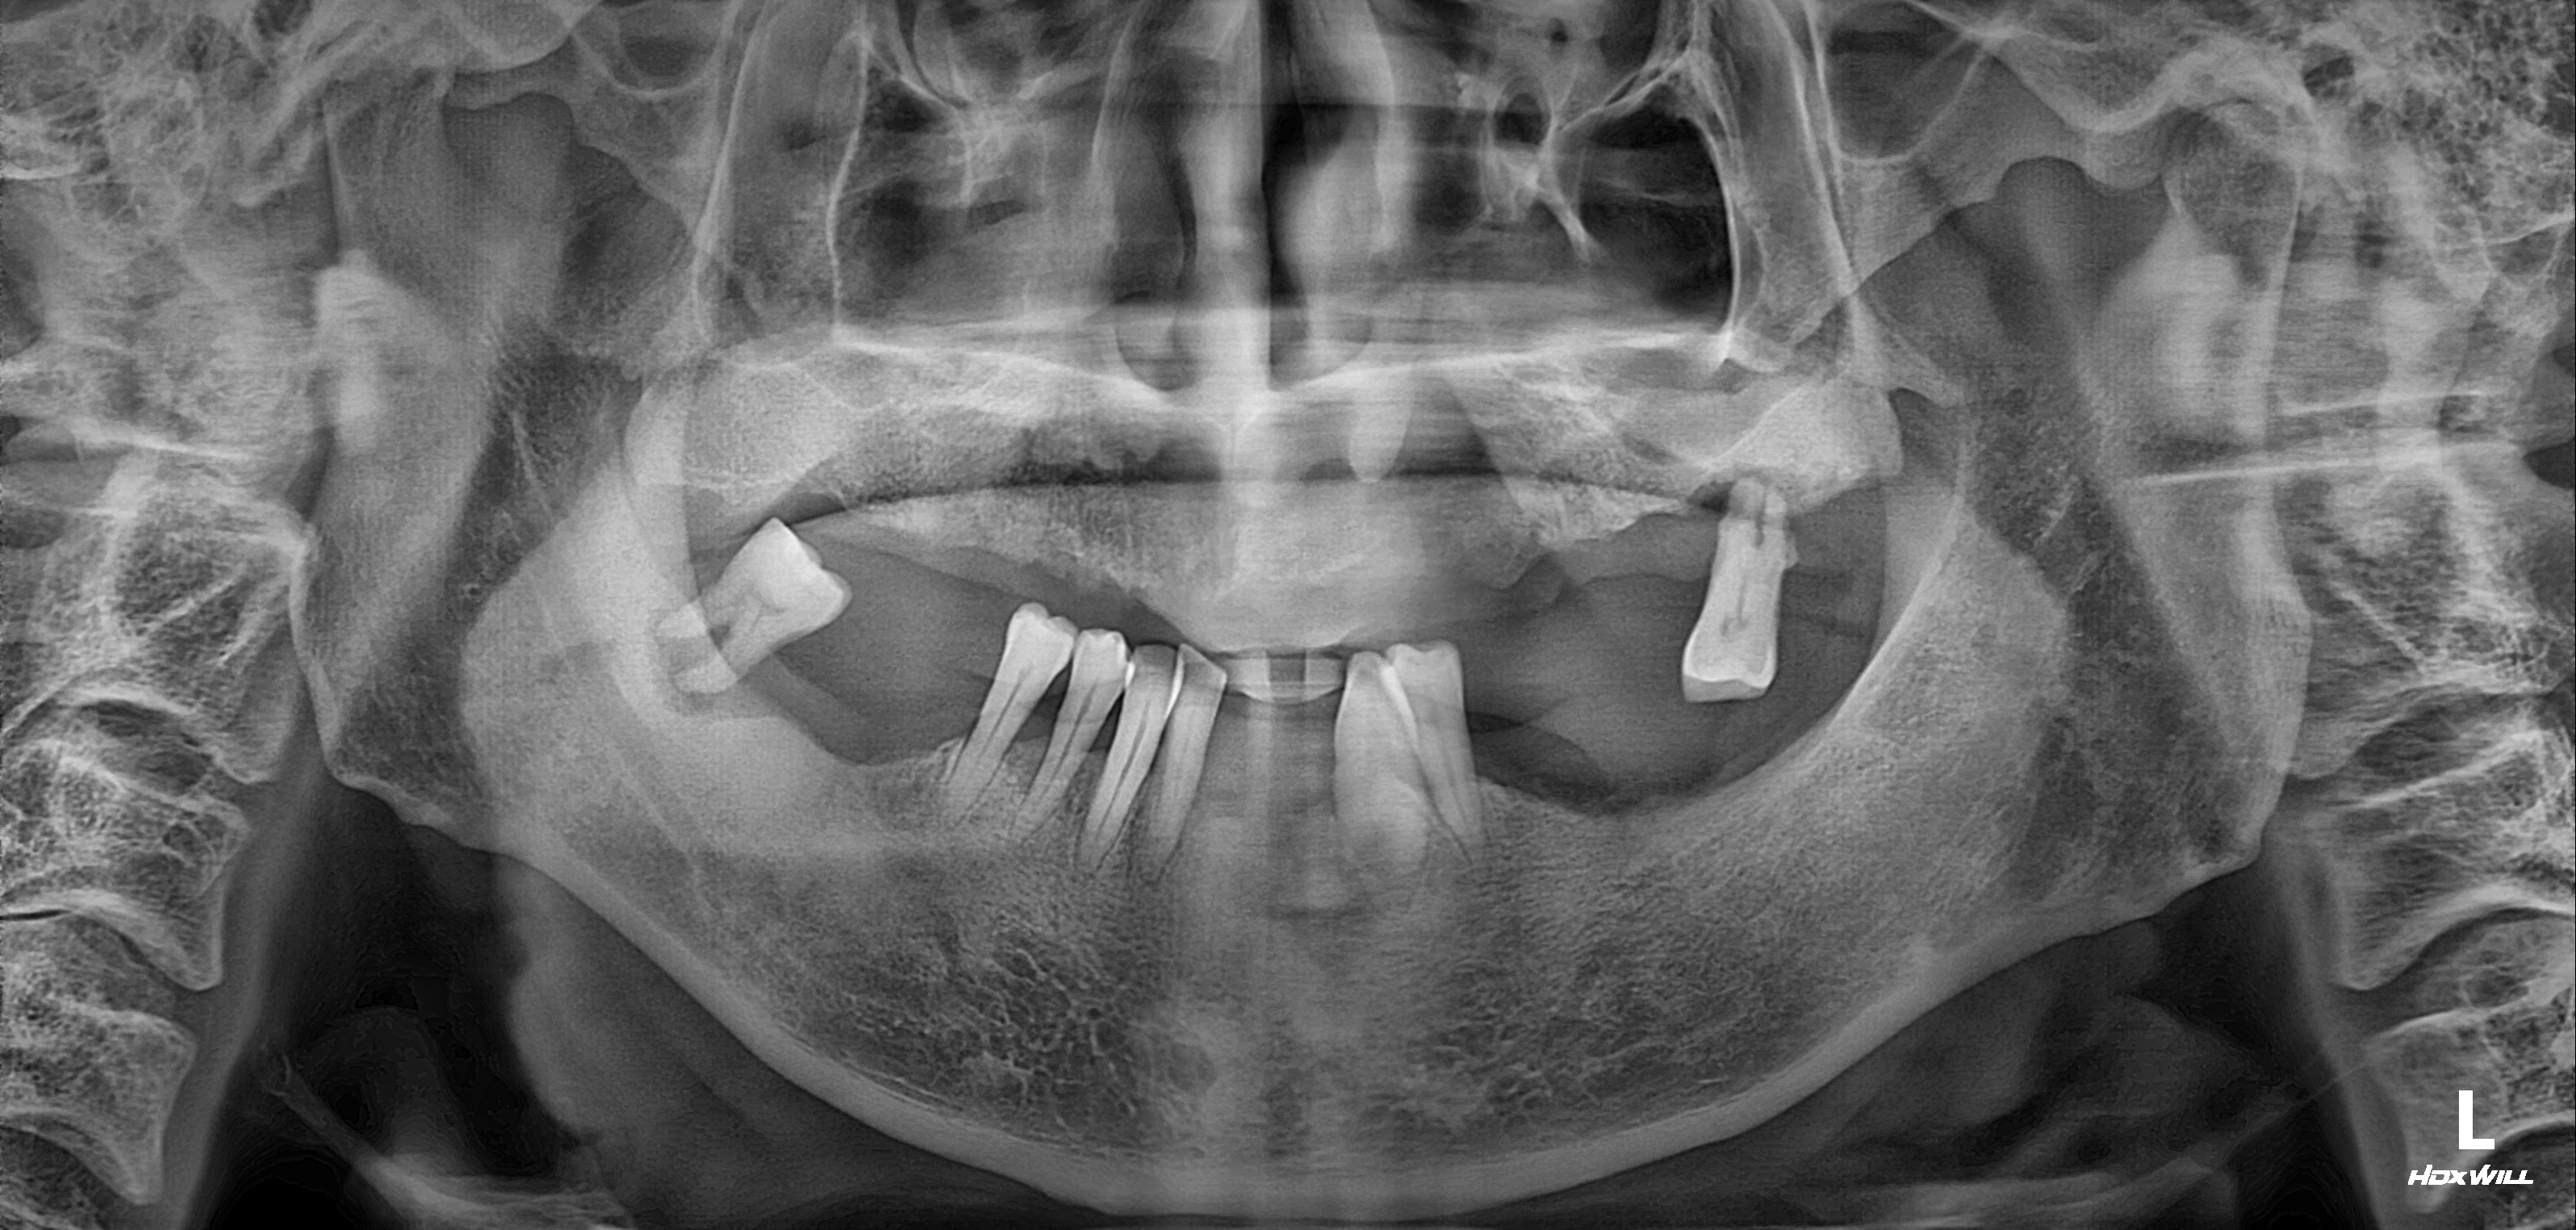

수술 전

수술 후

하악 전체+상악 부분 임플란트 식립사례

전후사진